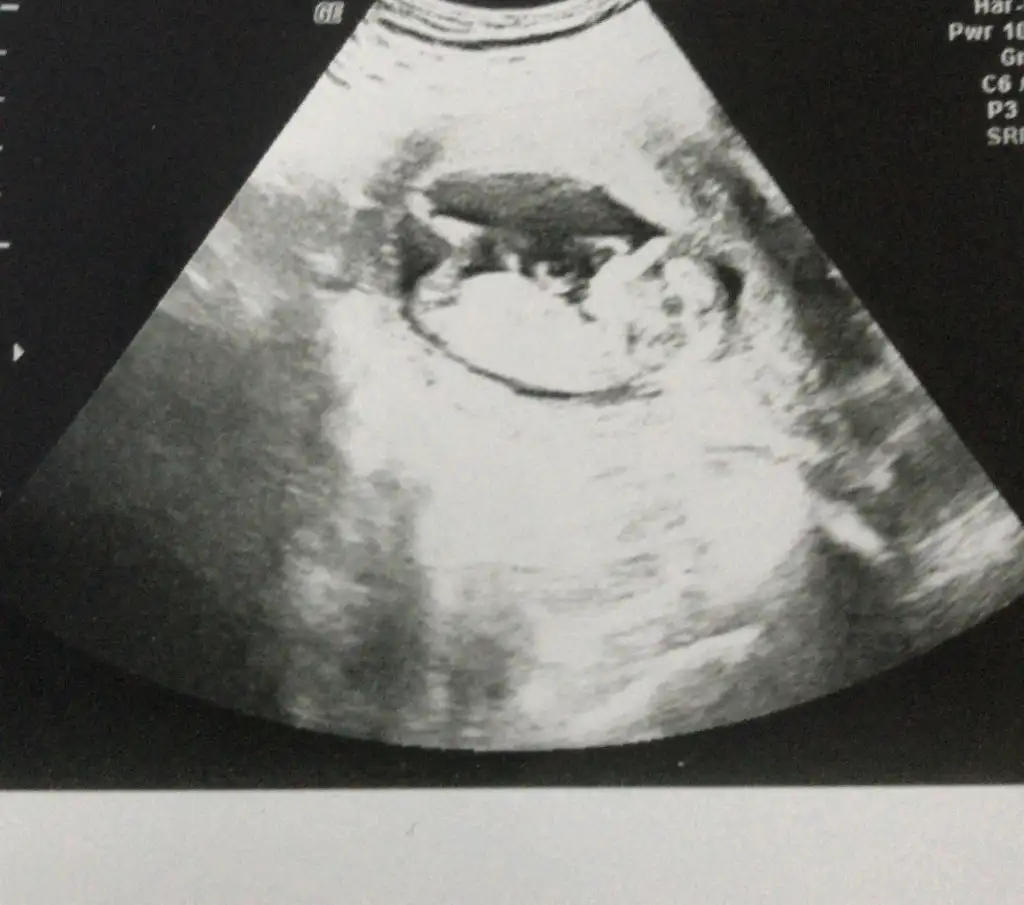

Erkek gibi sankiBenimki kiz demi![]()

Bide bu var ayni bebek duz gibi geliyor bana amaErkek gibi sanki

Burada tam dik değil acısı paralelde değil karşıya bakıyor pozisyon degistirmiyorsa kız olabilirBide bu var ayni bebek duz gibi geliyor bana ama![]()

kıza benziyoBide bu var ayni bebek duz gibi geliyor bana ama![]()